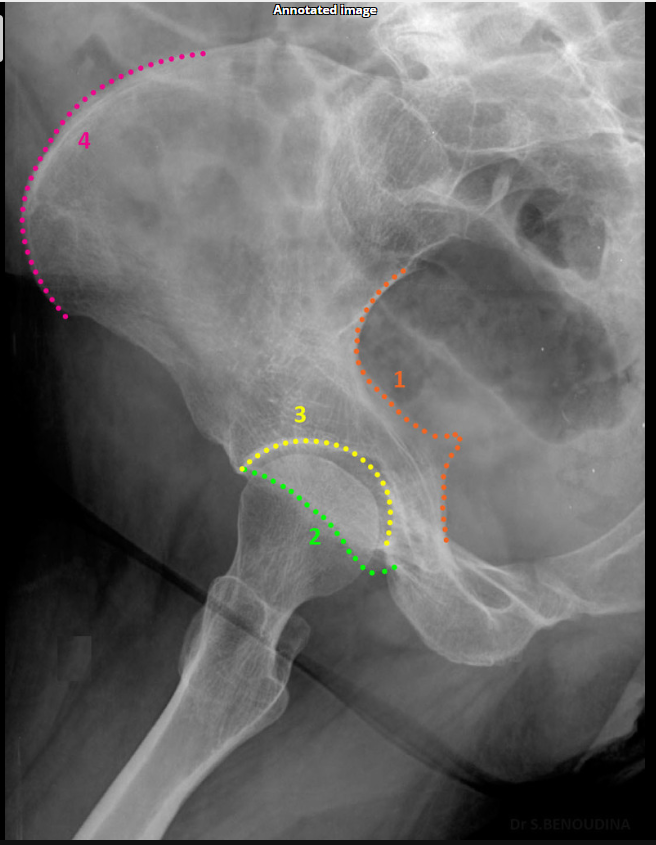

Which acetabular rim does the internal oblique Judet view show?

Posterior rim. (SHOWN #2 PURPLE)

Anterior column. (SHOWN #1 RED)

Which acetabular rim does the external oblique Judet view show?

Anterior rim. (SHOWN #2 GREEN)

Which acetabular column does the external oblique Judet view show?

Posterior column.ilioschial(SHOWN #1 ORANGE)

What does the iliopubic line represent in Judet views?

Anterior column.(SHOWN #1 RED)

What does the ilioischial line represent in Judet views?

Posterior column.(SHOWN #1, ORANGE)